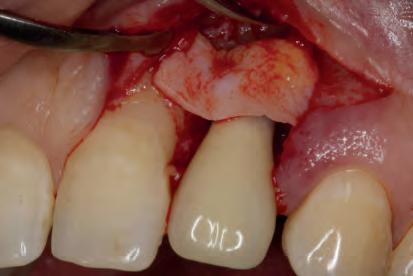

MANAGEMENT OF PERI-IMPLANTITIS IN THE AESTHETIC ZONE

The management of peri-implantitis cases in aesthetically demanding areas is a highly relevant clinical challenge due to the increased risk of mucosal recessions subsequent to the treatment. The exposure of the implant surface may result in an aesthetically unacceptable outcome. Thus, the additional goal of peri-implantitis management in aesthetic areas is the preservation of the esthetics.

The lecture will elaborate on the remodeling process that peri-implant tissue undergoes following the surgical peri-implantitis treatment. It will further address the step-by-step surgical treatment protocol for the management of peri-implantitis cases in the aesthetic zone and the rationale for soft-tissue grafting as part of the treatment protocol. Clinical scenarios resulting in unacceptable aesthetic outcomes requiring implant removal and the “second-round” implant planning will be further discussed.